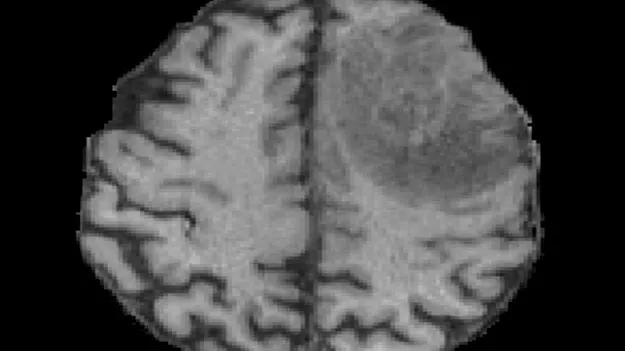

కంది, హైదరాబాద్‌, డిసెంబరు 30 (ఆంధ్రజ్యోతి): మెదడు క్యాన్సర్‌ పేషంట్లు ఆ వ్యాధి నుంచి కోలుకునే అవకాశాల్ని.. ఎంఆర్‌ఐ స్కాన్‌ల ద్వారా అంచనా వేసి చెప్పే వెబ్‌ ఆధారిత టూల్‌ని ఐఐటీ హైదరాబాద్‌ పరిశోధకులు రూపొందించారు. దీనికి ‘రేడియాలజీ ఆఫ్‌ గ్లియోమా’ అని పేరు పెట్టారు. ఎంఆర్‌ఐ ఇమేజీల్లో కంటికి కనిపించని అతి సూక్ష్మ అంశాలను కూడా ఇది గుర్తించగలుగుతుందని, తద్వారా రోగి పరిస్థితిని కచ్చితంగా అంచనా వేస్తుందని పరిశోధనకు నేతృత్వం వహించిన ఐఐటీహెచ్‌ అసిస్టెంట్‌ ప్రొఫెసర్‌ రాహుల్‌ కుమార్‌ తెలిపారు. మెదడు క్యాన్సర్‌ చికిత్సలకు ‘రేడియాలజీ ఆఫ్‌ గ్లియోమా’ సహకారిగానే ఉంటుందిగానీ ప్రత్యామ్నాయం కాదని స్పష్టం చేశారు. ఇప్పటికీ బయాప్సీనే.. క్యాన్సర్‌ చికిత్సలో అత్యంత కీలకమని తెలిపారు. ఈ పరిశోధనలో పాలుపంచుకున్న కవిత కుండల్‌ మాట్లాడుతూ, ఈ ప్రాజెక్టులో ఎంఎన్‌జే క్యాన్సర్‌ ఆస్పత్రి భాగస్వామిగా ఉందన్నారు. ఆ ఆస్పత్రి సహకారంతో 50 మంది పేషంట్ల ఎంఆర్‌ఐ స్కాన్‌లను తాము అధ్యయనం చేశామని, రానున్న రోజుల్లో మరో 100 ఎంఆర్‌ఐ స్కాన్‌లు వచ్చే అవకాశం ఉందని తెలిపారు. ఈ పరిశోధనలో ఢిల్లీ ఎయిమ్స్‌ కూడా పాలుపంచుకుంటోందన్నారు. పరిశోధన వివరాలు ‘ఎన్‌పీజే ప్రిసిషన్‌ ఆంకాలజీ’ మ్యాగజైన్‌లో ప్రచురితమయ్యాయి.